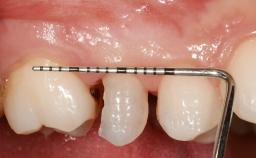

Early Placement of an Implant in a Maxillary Right Central Incisor Site

This 41-year-old female patient was referred to the clinic for the replacement of the right central incisor, since the tooth had developed a root fracture in the long axis that made extraction necessary. The healthy, non-smoking patient was first seen with the tooth still in place. A detailed Esthetic Risk Assessment was performed.The patient was worried about her dental esthetics and had high expectations for a successful treatment outcome from an esthetic point of view. The patient had a medium lip line that displayed parts of the gingiva in the anterior maxilla upon smile.

| Bone Level at Adjacent Teeth | <= 5 mm to contact point | 5.5 to 6.5 mm to contact point | > 7 mm to contact point |